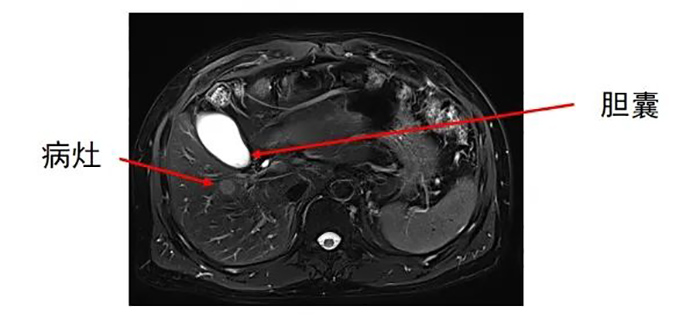

肝内转移灶数目为两个,分别位于左叶和右叶。

准确插入到病灶内,并避开了门静脉右支及胆,避免了出血、损伤胆囊等并发症。